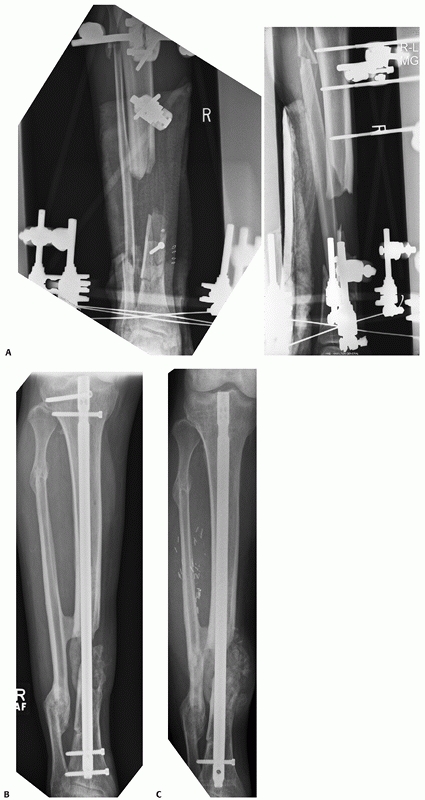

the operative treatment of closed tibial shaft fractures, there is

still a significant proportion of surgeons who opt to use external

fixation in the management of the severely traumatized limb. This is

usually in open tibial shaft fractures, fractures associated with

compartment syndrome, or in the polytraumatized patient who is deemed

too hemodynamically unstable to undergo definitive fixation (Fig. 55-13).

External fixation frames in tibial shaft fractures can take the form of

uniplanar monoaxial frames that use Schanz pins above and below the

fracture site, multiplanar external frames that use configurations that

place the Schanz pins in different planes, which are usually

orthogonal, and the use of circular tensioned fine wire external

fixation frames, or a combination of both tensioned fine wire circular

frames and half pin fixation. This is often referred to as hybrid

external fixation.

![]() |

|

FIGURE 55-13 A spanning external fixation frame used for the acute management of a type IIIB open proximal tibial shaft fracture.